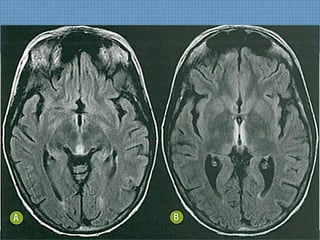

ACHADOS DE IMAGEM

• RM:  Determina diagnóstico e estima prognóstico;

– T1:Hipossinal em topografia subcortical parietoccipal, com

rara impregnação puntiforme pelo Gd;

– T2/FLAIR: Hiperssinal digitiforme parietocciptal, podendo

estender-se para as regiões cerebrais anteriores, além do

NB;

– SWI: Permite diagnóstico de hemorragia de permeio 

Hipossinal;

DIFUSÃO!

Usualmente normal  Só edema vasogênico;

Se restrição  Dano cerebral irreversível;

ACHADOS DE IMAGEM •RM:  Determina diagnóstico e estima prognóstico; – T1:Hipossinal em topografia subcortical parietoccipal, com rara impregnação puntiforme pelo Gd; – T2/FLAIR: Hiperssinal digitiforme parietocciptal, podendo estender-se para as regiões cerebrais anteriores, além do NB; – SWI: Permite diagnóstico de hemorragia de permeio  Hipossinal; DIFUSÃO! Usualmente normal  Só edema vasogênico; Se restrição  Dano cerebral irreversível;